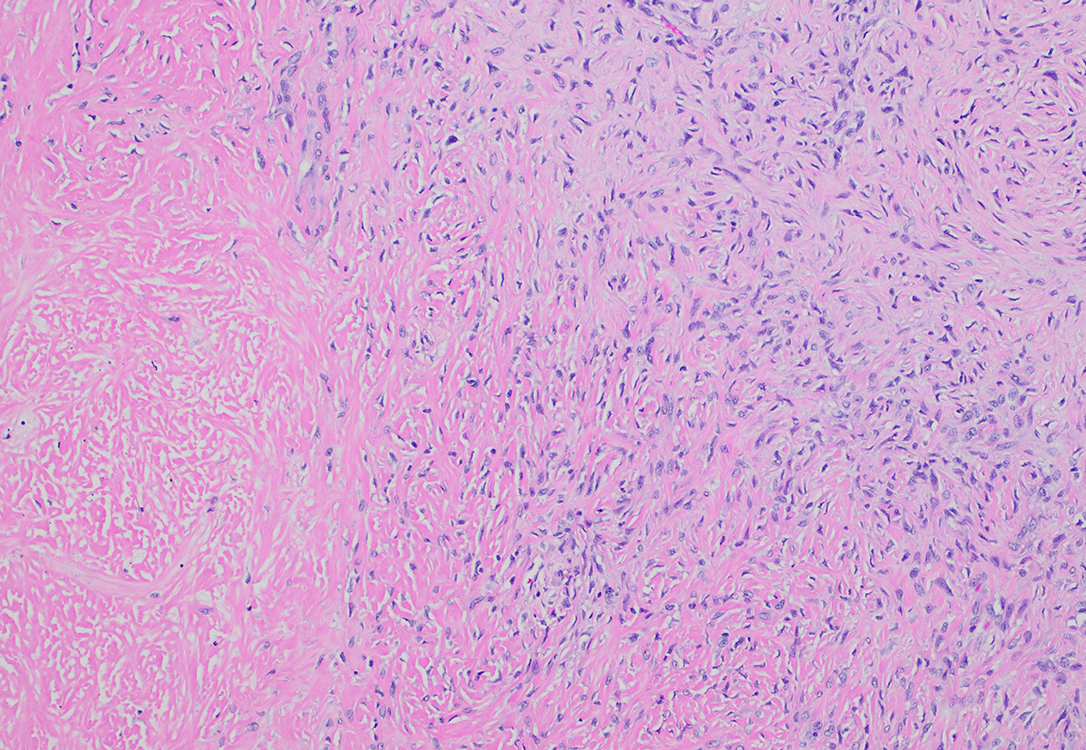

Figure 1 CT chest